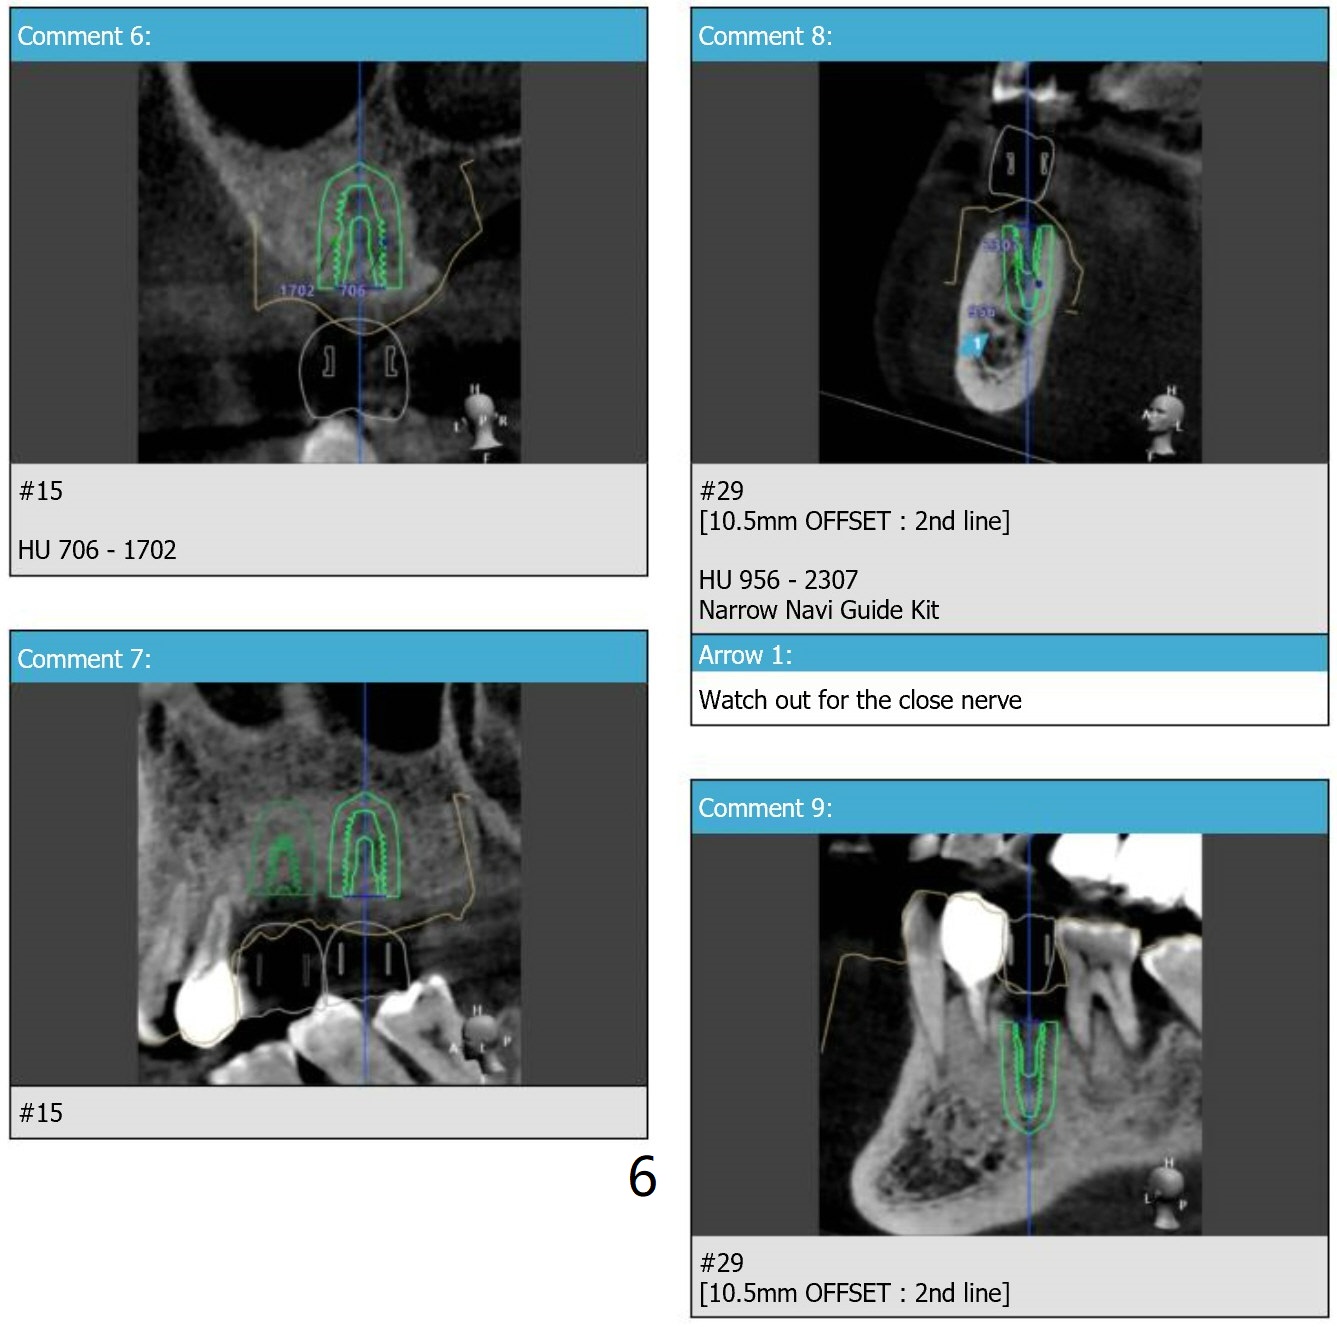

Return to Upper Molar Lower Premolar Immediate Implant, Trajectory